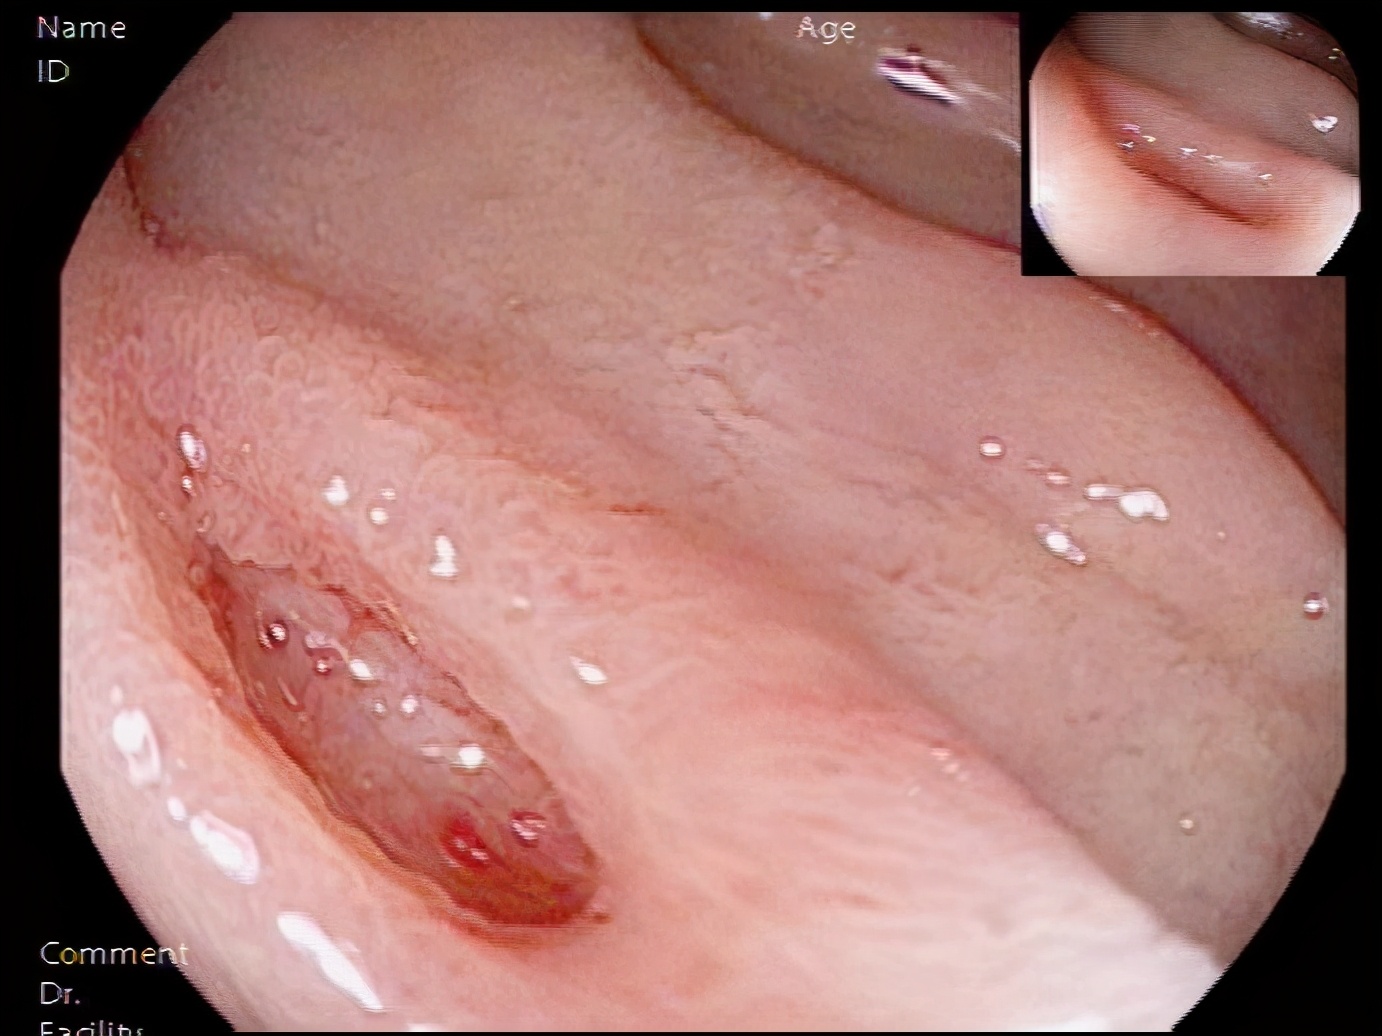

经过麻醉评估,15:40赵世民副主任医师开始内镜检查,发现患者十二指肠球降移行部有一处病灶,有活动性渗血,林涛主任指示行钛夹封闭创面治疗,于16:00顺利完成内镜下钛夹止血术。患者入院不到六小时就完成内镜下止血治疗,比急性上消化道出血救治快速通道国家标准的12小时缩短了6小时,体现了大兴速度。千方百计对患者好,用最短的抢救时间,最优质的医疗技术,给患者最优质的健康保障。

发现出血病灶